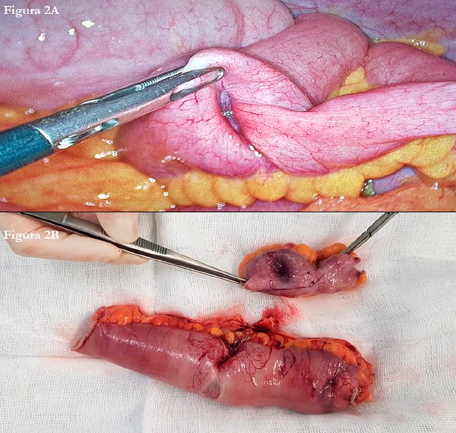

Alejandro David Bueno Cañones, Martín Bailón Cuadrado, Enrique Asensio Díaz, David Pacheco Sánchez

|

|

|